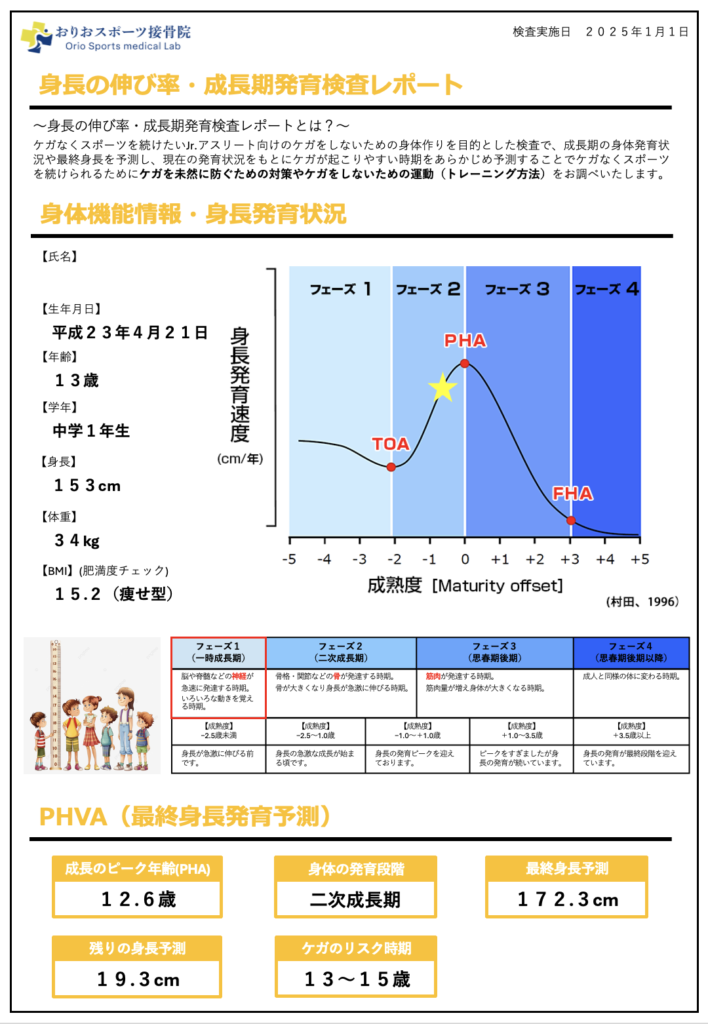

成長発育検査でケガのリスクを予測

成長期のお子さんには、成長発育検査も実施しています。これは、身長の伸び率を測定し、今後どのくらい身長が伸びるか、ケガが起こりやすい時期がいつ頃かを予測する検査です。

身長が急激に伸びる時期は、クラムジー現象が起こりやすく、ケガのリスクが高まります。この時期を事前に予測しておくことで、練習量を調整したり、ケアを強化したりすることができます。

S様の成長発育検査の結果、今後1年ほどは身長の伸びが大きい時期が続くと予測されました。そのため、この時期は特に柔軟性の維持やバランストレーニングを重視し、ケガの予防に努めることが重要です。